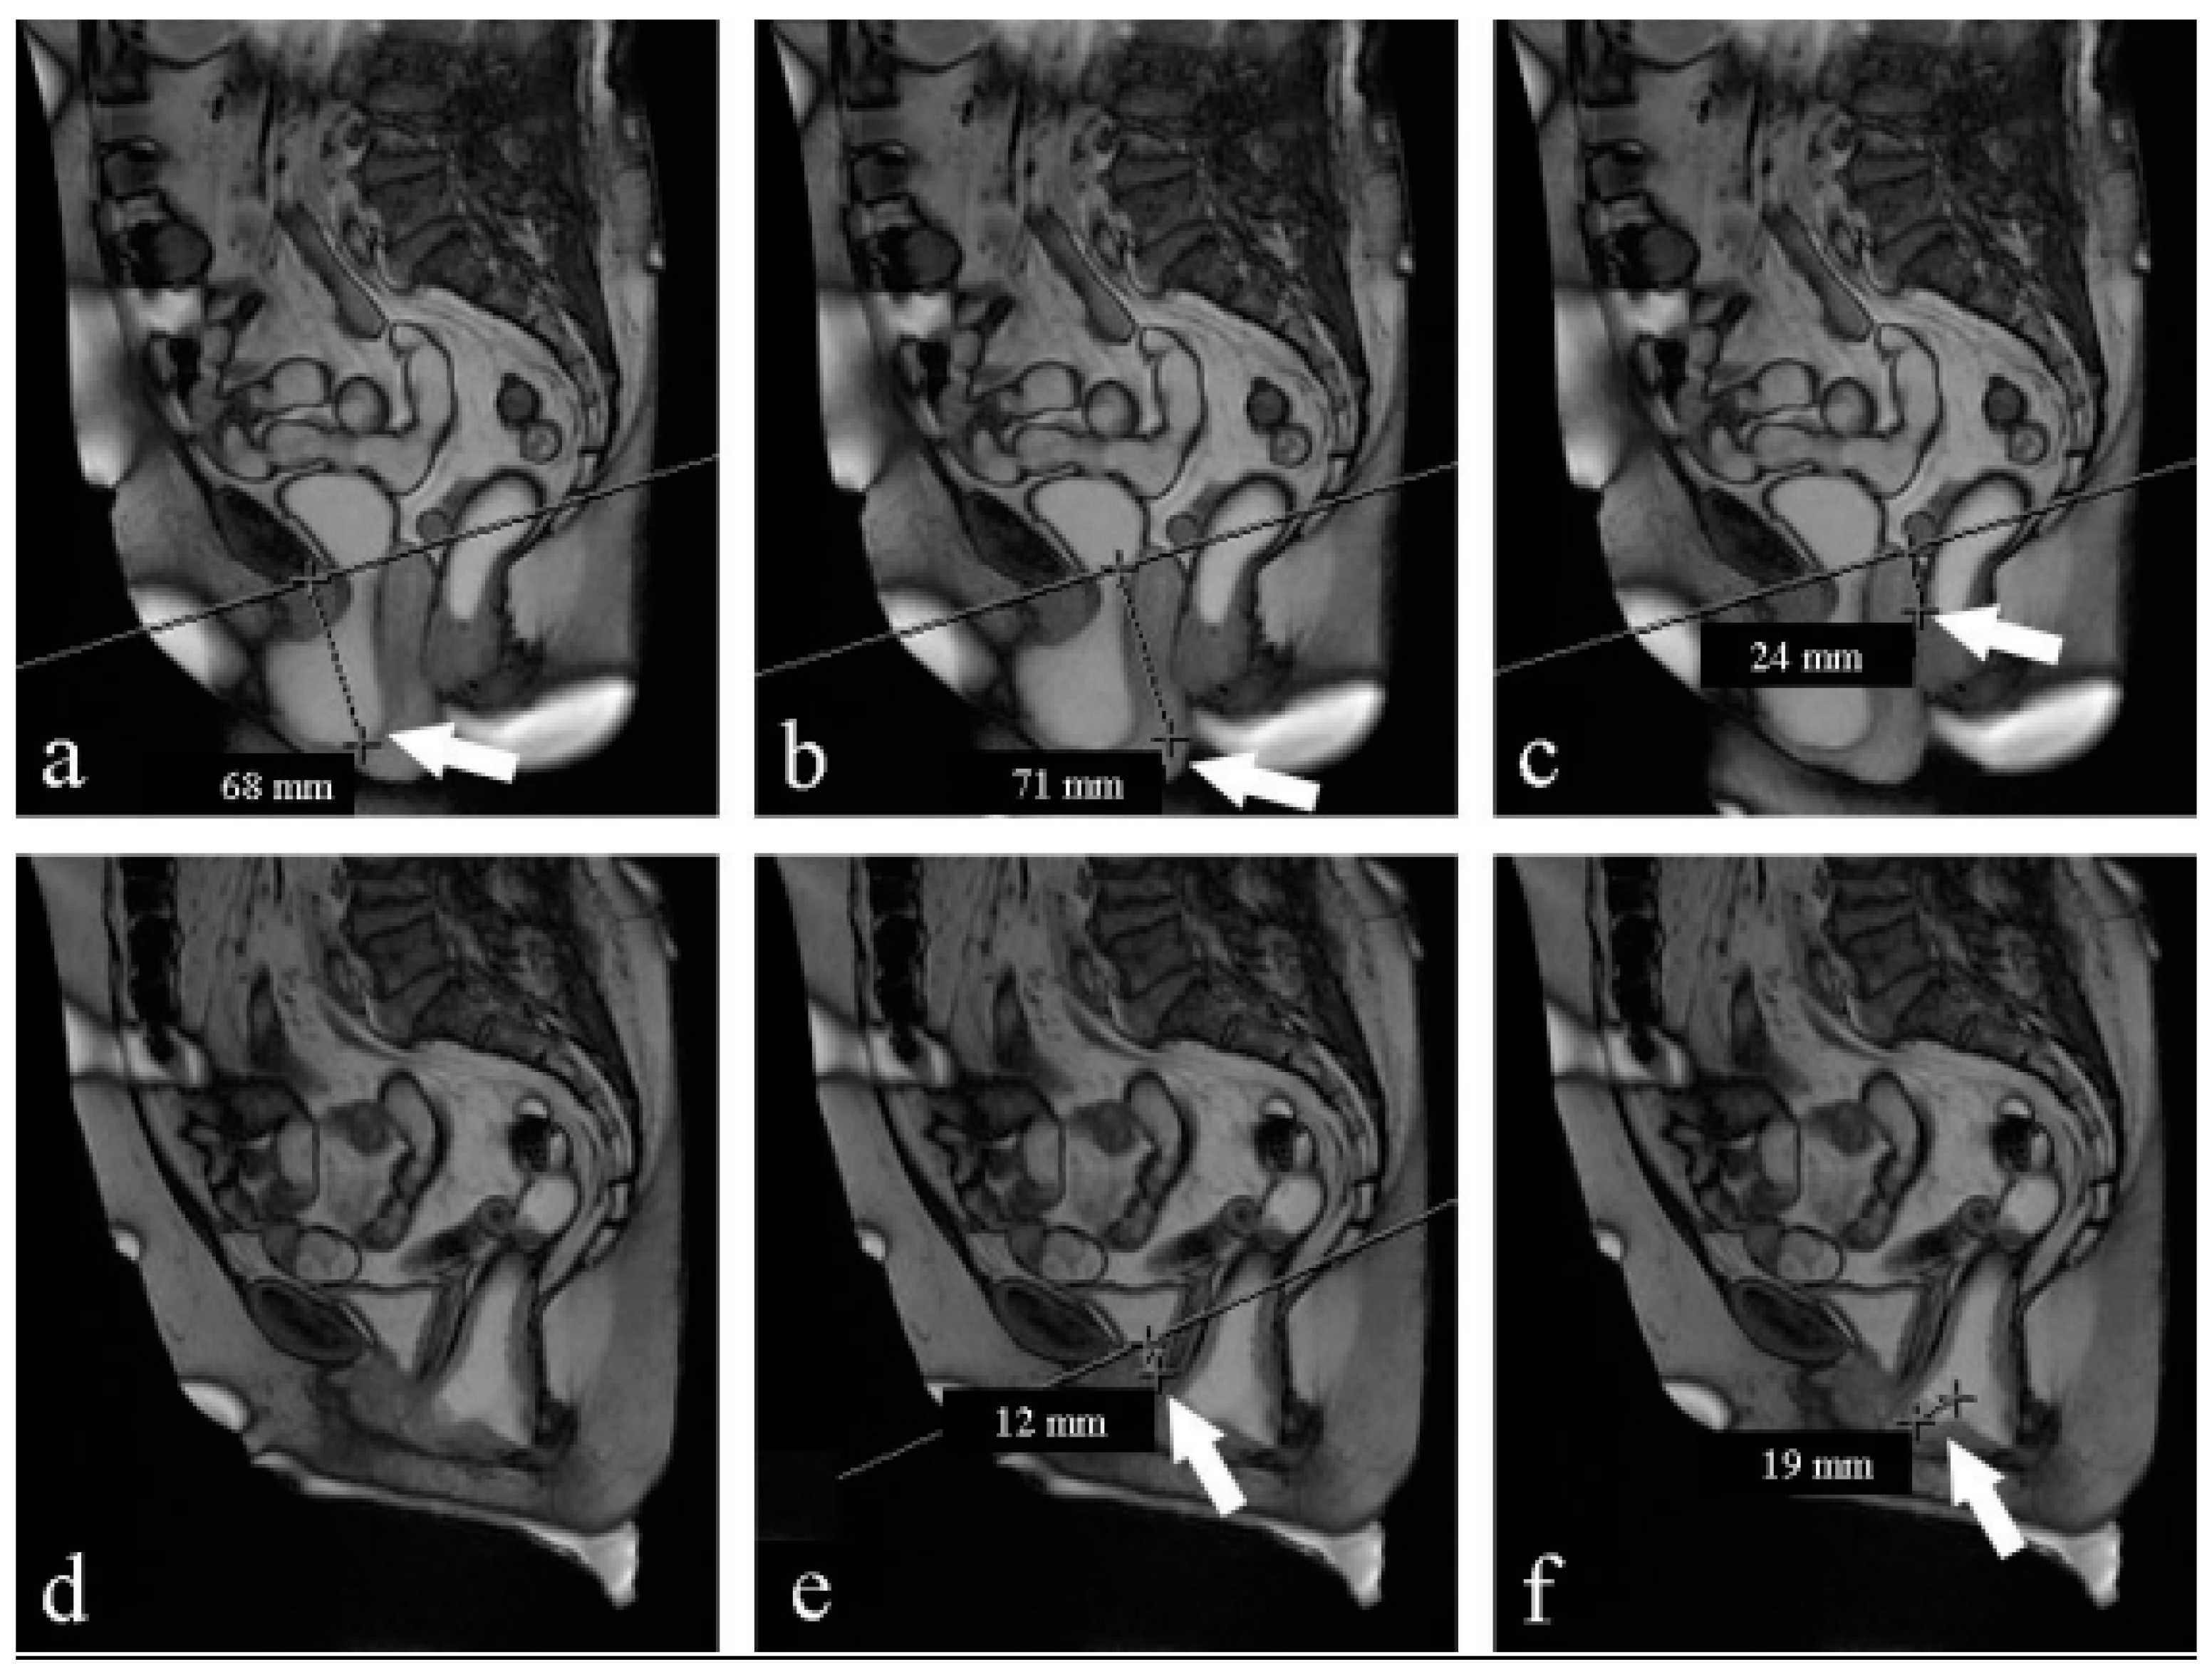

- Pubococcygeal line (PCL): a line drawn from the inferior margin of the pubic symphysis to the last coccygeal joint [16];

- Levator plate angle (LPA): enclosed between the levator plate and the PCL where the ileo-coccygeus touches the coccyx. It is usually 11.7° ± 4.8 in healthy women under the Valsalva maneuver [16].

- The H-line: extends from the inferior aspect of the pubic symphysis to the anorectal junction, represents the genital hiatus: on effort, it is 5.8 cm ± 0.5 [19].

- The M-line: dropped as a perpendicular line from the PCL to the posterior aspect of the H-line: normally on effort, it is 1.3 cm ± 0.5 [19].

| Valsalva | Pre Average ± DS | Post Average ± DS | p |

|---|---|---|---|

| PCL (mm) | 103.3 ± 11.26 | 102.6 ± 11.96 | 0 |

| H-line (mm) | 82.2 ± 11.75 | 77.6 ± 12.75 | 0.008 |

| M-line (mm) | 69.8 ± 6.42 | 65 ± 9.64 | 0.001 |

| LPA (°) | 50.7 ± 9.5 | 44.7 ± 11.12 | 0.001 |

| VUA (°) | 130 ± 68 | 187.4 ± 53.32 | 0.59 |